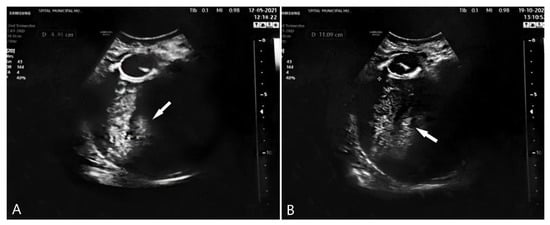

2. Case Presentation